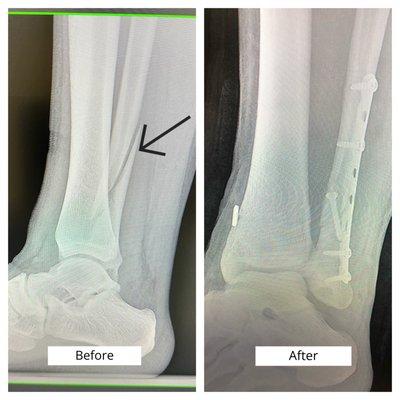

Kim Jong DPM at Riverside Medical Center is a dedicated podiatrist located in Riverside CA. Specializing in foot and ankle care Dr. Kim offers comprehensive services to address various podiatric conditions. Patients can expect a welcoming environment and personalized treatment plans aimed at promoting overall foot health.